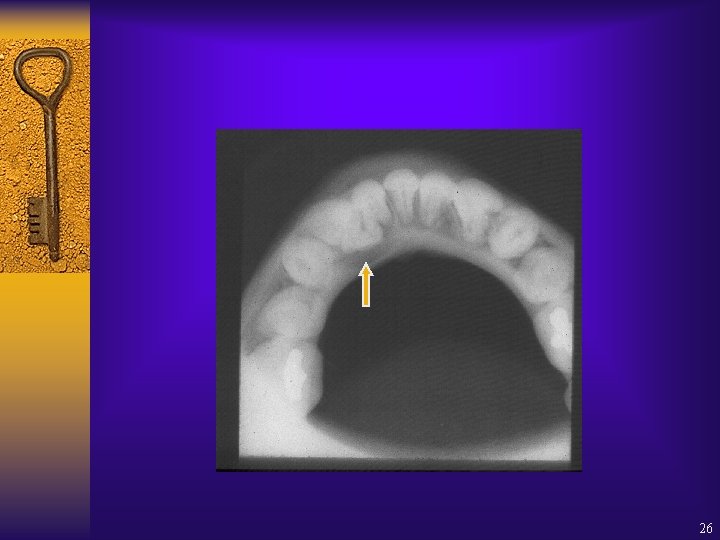

26